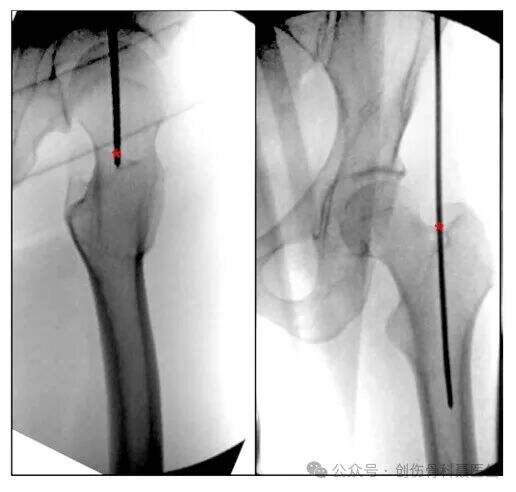

④ Retrograd interlockande intramedullär nailing för lårbenfrakturer

INDIKATIONER: Främst indikerat för supracondylära lårbenfrakturer, inklusive komminuerade supracondylära frakturer och intercondylära "T"- och "Y"-typs komminuerade frakturer som involverar ledytan. Även lämpligt för lårbenfrakturer distalt till isthmus, inklusive frakturer i distala lårbenets skenben, supracondylära regionen och intercondylära regionen, vanligtvis inom 20 cm från knäleden.

Patientpositionering: Liggande ställning.

Insision & införingspunkt: Med knäet böjt ca 30° ligger den ideala införingspunkten i mitten av intercondylära taket, ca 1,2 cm framför lårbenets fästpunkt för det bakre korsbandet (i linje med axeln på märggången).